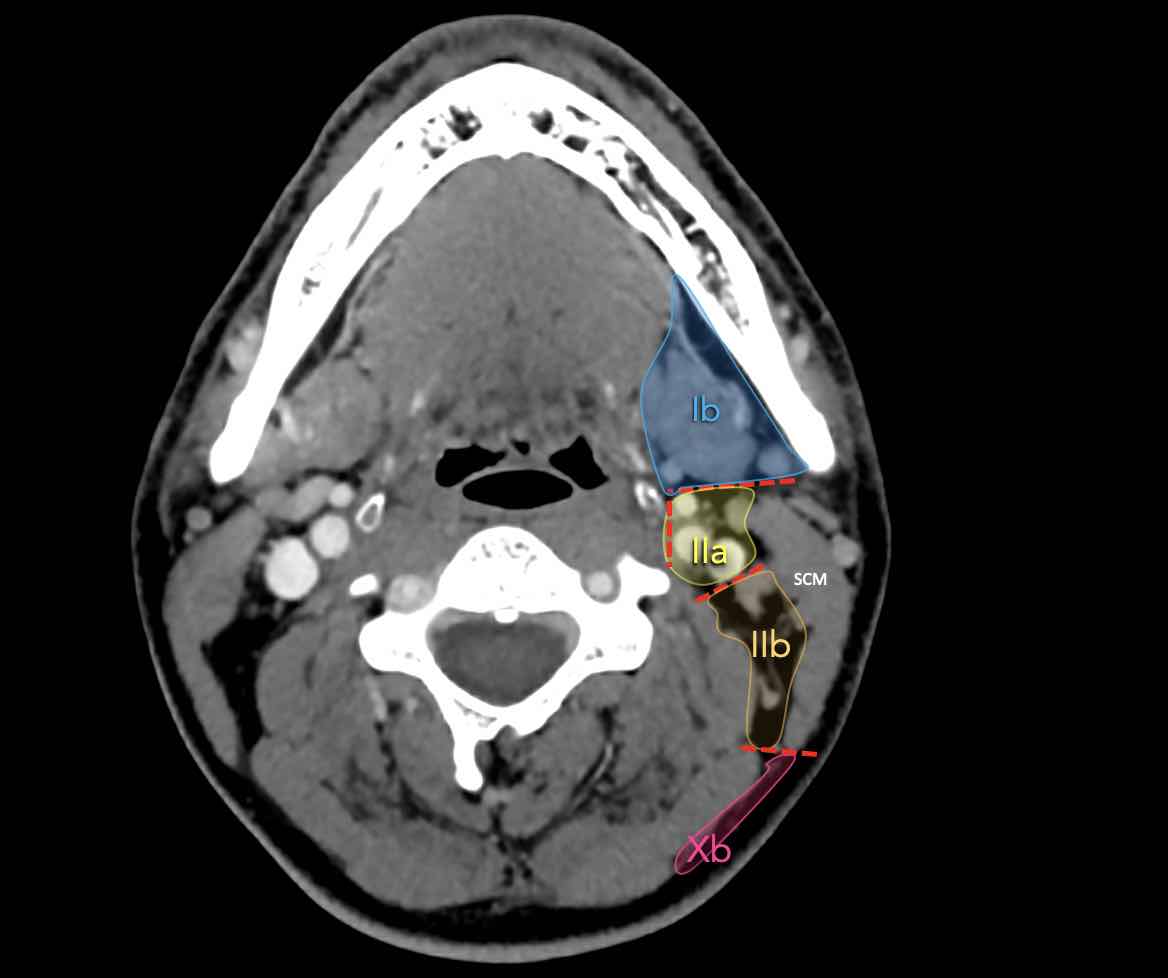

Tầng Ib

chứa các hạch dưới hàm nằm trong khoang giữa mặt trong của xương hàm dưới ở phía ngoài và cơ nhị thân ở phía trong, từ khớp mu cằm ở phía trước đến tuyến dưới hàm ở phía sau.

Tầng II có thể được chia thành tầng IIa và tầng IIb bằng cách vẽ một đường tại bờ sau của tĩnh mạch cảnh trong.

Các hạch bạch huyết ở tầng IIa và IIb có nguy cơ chứa di căn từ các ung thư hốc mũi và khoang miệng, vòm hầu, hầu miệng, hạ hầu, thanh quản và các tuyến nước bọt lớn.

Tầng IIb thường liên quan hơn đến các khối u nguyên phát ở hầu miệng hoặc vòm hầu, và ít thường xuyên hơn với các khối u ở khoang miệng, thanh quản hoặc hạ hầu [1].